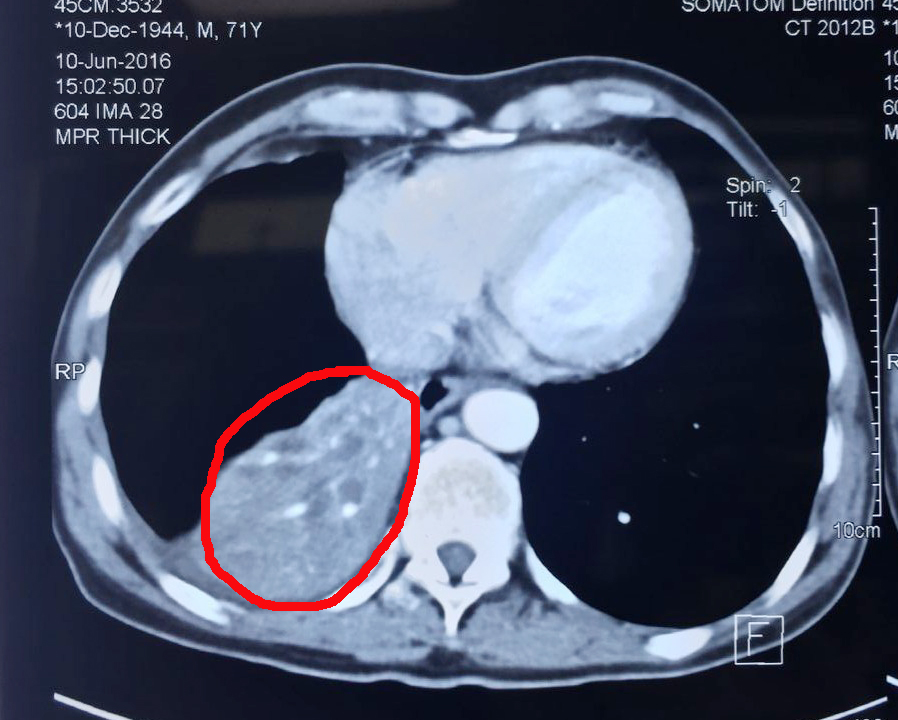

肿瘤治疗前